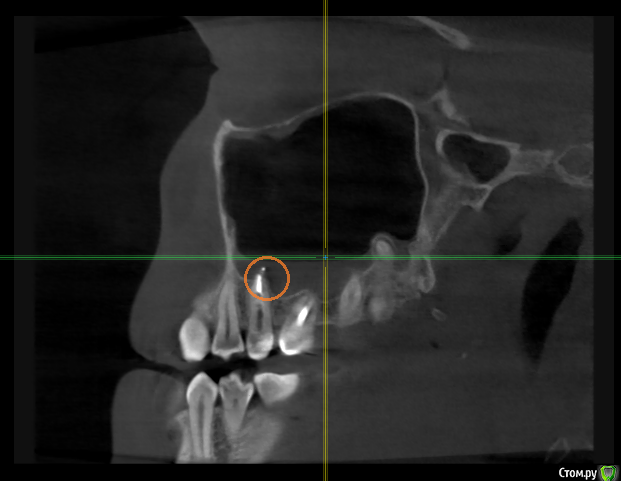

alexandrovna Опубликовано 8 ноября, 2015 Поделиться Опубликовано 8 ноября, 2015 (изменено) Здравствуйте! Помогите, пожалуйста, мучаюсь уже почти год. Здесь были мои темы, последнюю попросила закрыть, думала пойду уже удалять зуб, даже записалась, но решила напоследок еще к лору сходить. Начну от печки, так понятнее будет. В декабре 2014 поменяла пломбу в зубе 26 и он тут же заболел при накусывании. Через 2 месяца мне его наконец вскрыли, сказали пульпит, полечили каналы (поставили эндометазон). Зуб при накусывании не прошел. В мае снова перелечили, поставили гуттаперчу и оставили проходить под временной пломбой. 18 июля пришла к доктору, 26 при накусывании еще не прошел (но болел меньше), решили перелечить зуб 25, мне его обточили при предыдущем лечении 26 (у 25 каналы запломбировали 9 лет назад, зуб не беспокоил, на снимке все было хорошо, но при снятии пломбы доктору не понравилось то, что внутри). Во время промывания почувствовала резкую боль в ухе и пазухе, ощущение воды в левой пазухе, левую ноздрю заложило. Как мне доктор объяснил - анатомия, корни в пазухе, в пазуху попадал хлоргексидин, все пройдет. И с 18 июля по сегодняшний день - закладывает периодически левую ноздрю, высмаркивается прозрачная слизь с белыми включениями, болит левая половина лица, левый глаз изнутри, при сморкании левый глаз дергается, зубы 25-27 болят при накусывании (особенно 26, он заболел по новой ужасно), зубы 21-27 как будто онемевшие, скованные.Делала 2 раза КТ в августе и октябре (в расшифровке - у зуба 2.5 выход материала за пределы апекса в полость в/ч пазухи. Стоматолог мне назвал материал про-рут мта).Промывала нос три недели, пила антибиотики 2 раза-сумамед и кларитромицин, капала 2,5 месяца назонекс, пила нимесил, цетрин, лорагексал, синупрет.Я была у 2х ЛОРов - один предлагает удалить зуб 25 (и если не пройдет 26-его тоже), раз после его перелечивания начались проблемы с пазухой и из него торчит материал, другой ЛОР (вместе с челюстно-лицевым хирургом) - советуют лечь в больницу и попробовать сначала промыть пазуху, подозревают, как я поняла, ожог пазухи. Но это не панацея, конечно, просто на всякий случай, чтобы я потом не думала, удалив зуб, а что если бы я промыла....Подскажите, пожалуйста, 1. Что мне делать-удалить зуб и не мучаться или рискнуть и лечь в больницу на промывание пазухи? 2. Может ли это быть банальная аллергия на про-рут мта и как это проверить? И если это действительно аллергия-зуб опять же на удаление? 3. Взгляните, пожалуйста, на состояние костной ткани в области зубов 25-26 (я попробовала сделать срез)Спасибо. И может быть кто-то может мне что-нибудь посоветовать. Я совсем измучилась, если не сказать в отчаянии, ведь все началось с неправильно поменянной пломбы. Буду очень благодарна. КТ октябрь http://www.fayloobmennik.net/5502613 пароль 3101 Срез http://s017.radikal.ru/i417/1511/6b/6ba398f8b92e.pngЗаключение ЛОРа и ЧЛХ http://s017.radikal.ru/i431/1511/5e/19745b76345b.jpghttp://s015.radikal.ru/i332/1511/9f/9df5230a90e8.jpghttp://s020.radikal.ru/i712/1511/52/b71b50d46335.jpgЗаключение по КТ август http://s012.radikal.ru/i320/1511/f7/b64ddfdb83a5.jpghttp://i072.radikal.ru/1511/87/2476c1de7932.jpghttp://s020.radikal.ru/i715/1511/17/4c22d23fa20e.jpg Изменено 8 ноября, 2015 пользователем alexandrovna Ссылка на комментарий

St. Опубликовано 8 ноября, 2015 Поделиться Опубликовано 8 ноября, 2015 1. Что мне делать-удалить зуб и не мучаться или рискнуть и лечь в больницу на промывание пазухи? 2. Может ли это быть банальная аллергия на про-рут мта и как это проверить? И если это действительно аллергия-зуб опять же на удаление? 3. Взгляните, пожалуйста, на состояние костной ткани в области зубов 25-26 (я попробовала сделать срез Посмотрела КТ. Каналы в обоих зубах запломбированы красиво, выведение материала не критичное. Если там ПроРут, то по теории на него не бывает аллергии. Если хотите проверить, нужно попросить немного материала и отнести аллергологам для анализа.По поводу кости - ну кость как кость, ничего особенного не увидела. Если в будущем будет в этой области имплантация скорее всего понадобится синуслифт.Мне кажется стоит попытаться полечиться у ЛОРов консервативно и понаблюдать для начала. 1 Ссылка на комментарий